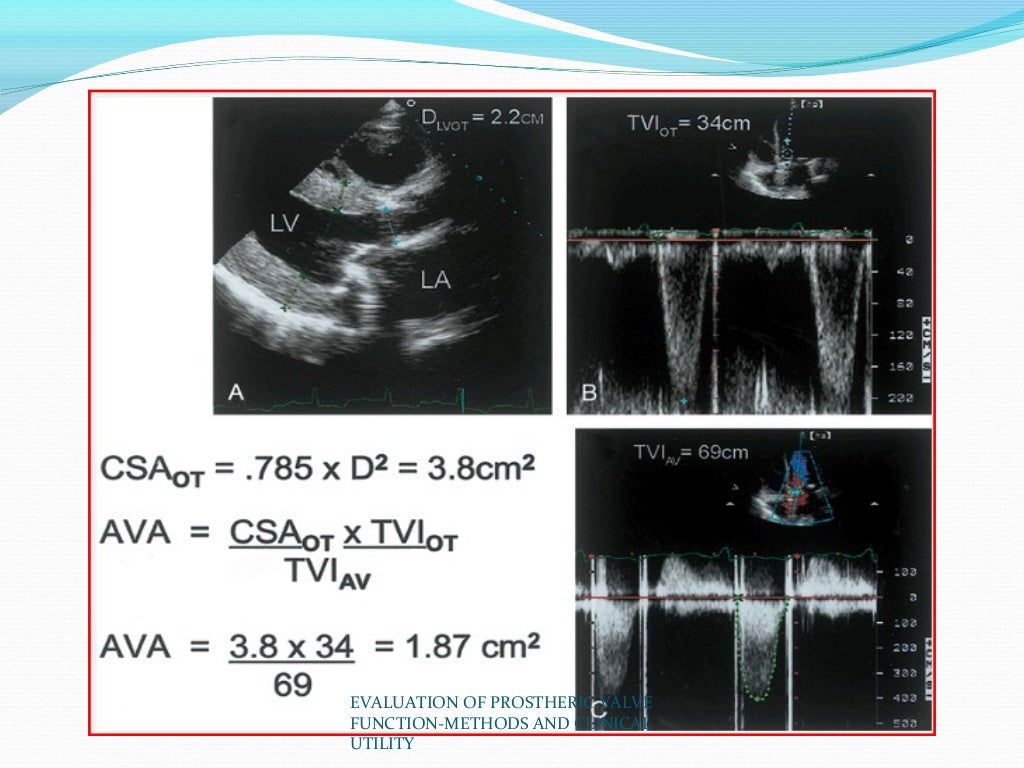

Evaluation Of Prosthetic Valve Function And Clinical Utility.

Evaluation of prosthetic valve function and clinical utility. www.slideshare.net

Brevet US20140052237 - Methods And Apparatus For Engaging A Valve